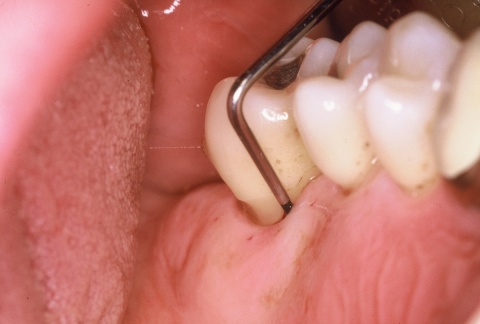

•IP1 – Mundhygienestatus: Darunter versteht man die Beurteilung der Mundhygiene mittels Anfärben der bakteriellen Beläge und der Benutzung eines geeigneten Index, z. B. des Approximalraumplaqueindex (Abb. 6). Für die Beurteilung des Gingivazustandes ist ebenfalls ein geeigneter Index anzuwenden, z. B. der Sulkusblutungsindex.

Im Regelfall werden die individualprophylaktischen Maßnahmen im Rahmen einer einsatzvorbereitenden Prophylaxesitzung durchgeführt. Die Besonderheiten des Einsatzes können Auswirkungen auf das individuelle Mundhygieneverhalten der Soldaten/innen haben, sodass die Durchführung der beschriebenen Maßnahmen im zeitlichen Zusammenhang zum bevorstehenden Einsatz sinnvoll ist. In Abhängigkeit von den jeweiligen klinischen Befunden kann die Entfernung harter und weicher Beläge in dieser Sitzung indiziert sein (Abb. 7). Die Entscheidung darüber trifft jeweils der SanOffz/Zahnarzt.